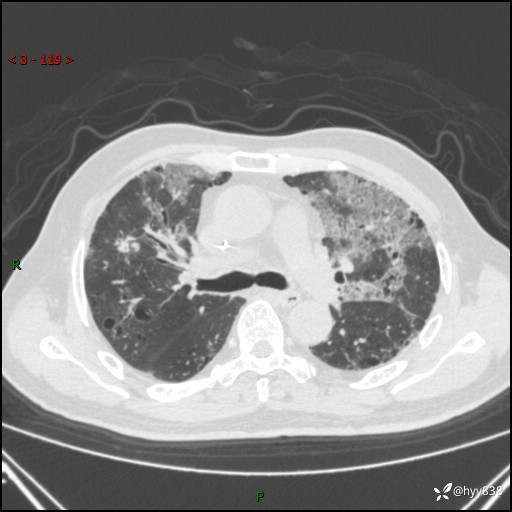

患者性别:男

患者年龄:64岁

简要病史:肝内胆管癌综合治疗后2周余,咳嗽、发热,咳白色泡沫痰。

辅助检查:CT

临床诊断:感染?

讨论:病变性质?